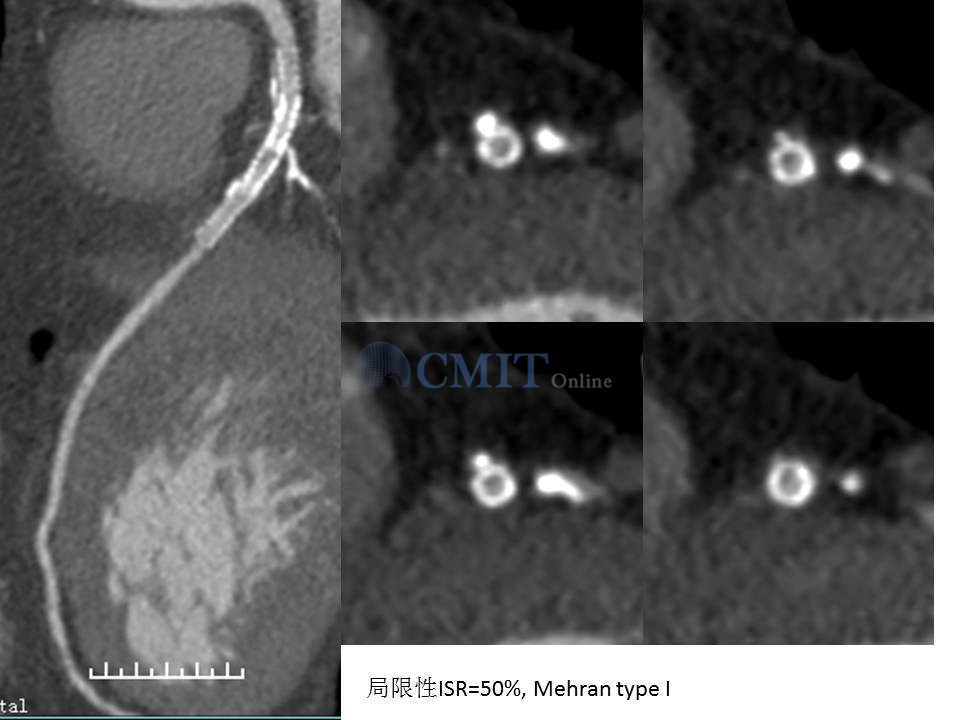

冠脉CTA读片技巧:如何判断支架内再狭窄?